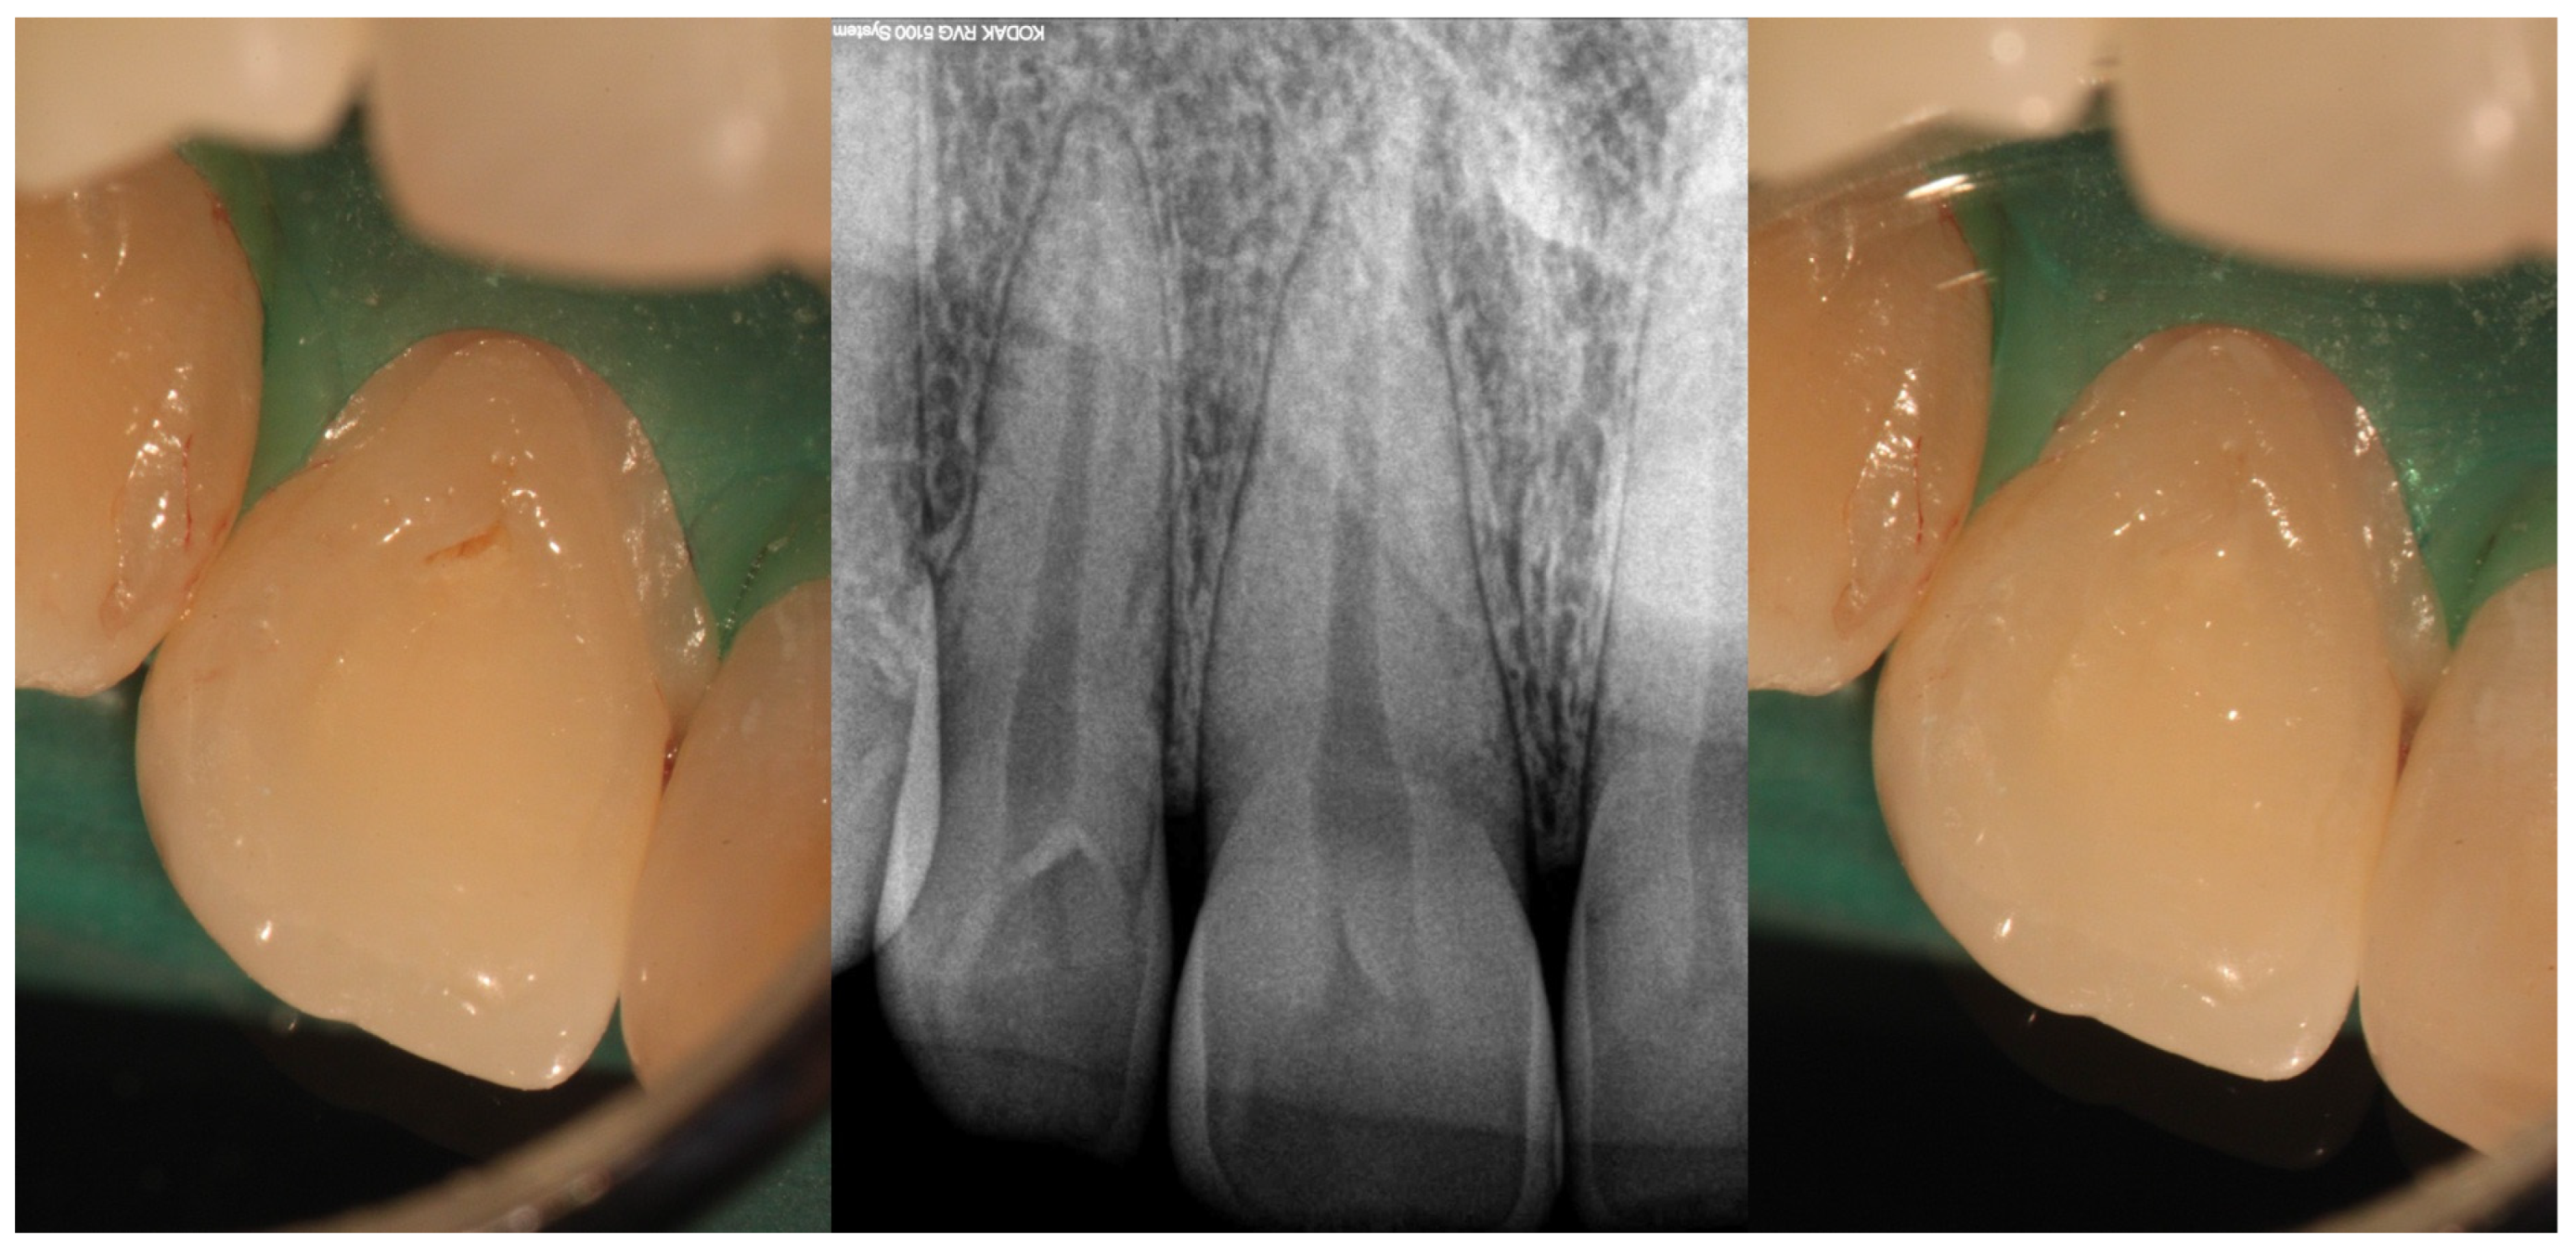

- Pires, M.D.; Baruwa, A.O.; Martins, J.N.; Quaresma, S.A.; da Costa, R.P.; Ginjeira, A. Endodontic management of developmental anomalies: Conservation of invaginated tissues in Type II dens invaginatus–case series. Rev. Port. Estomatol. Med. Dent. Cir. Maxilofac. 2019, 60, 18–26. [Google Scholar] [CrossRef]

| Type II | Moderate to high risk of pulp involvement | CBCT recommended to assess depth and pulp communication | Preventive sealing or minimally invasive restoration If pulp compromised, vital pulp therapy or root canal treatment depending on health state of pulp | Good to fair prognosis if depth is within coronal third and detected early Radiographic follow-up needed to monitor healing |